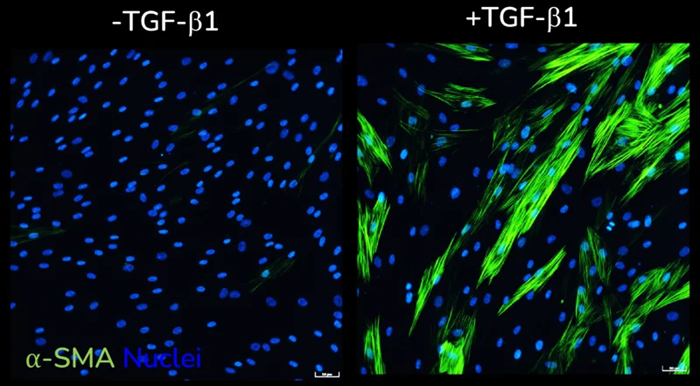

Functionally validated assay

- The assay’s functional validation demonstrates

- Increased expression of α-SMA

α-SMA expression in response to dose-dependent treatment with TGF-β1. Images were acquired using the ImageXpress Confocal HT.ai imaging system. Image Credit: Newcells Biotech

α-SMA expression without (left) and with (right) TGF-β1 stimulation of primary HLFs acquired using ImageXpress Confocal HT.ai imaging system, Scale bar: 50 µM. Image Credit: Newcells Biotech